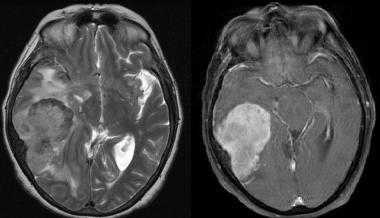

Менингиома височной области. На серии последовательных МР-изображений видно крупное образование правой височной области с паттерном контрастирования по типу «колеса со спицами», местным объемным воздействием, отеком окружающих тканей и гиперостозом подлежащей кости.

Атипичная с деструкцией пирамиды височной кости. На корональном Т2-взвешенном и контрастированном Т1-взвешенном МР-изображении виден быстрый рост конвекситального объемного образования в сторону намета мозжечка и пирамиды височной кости.

Менингиома теменной области. МР-изображения, полученные с использованием следующих последовательностей: аксиальное Т2-взвешенное, аксиальное Т2-взвешенное, корональное FLAIR -изображение и сагиттальное Т1-изображение. Крупная левосторонняя менингиома выглядит в виде экстрааксиального образования с паттерном «колеса со спицами» и отеком окружающих тканей.